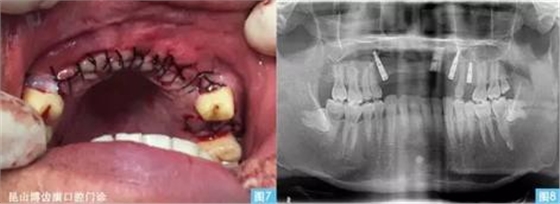

圖7圖8:(左圖7)黏膜對(duì)位縫合,(右圖8)種植術(shù)后曲面體層攝影。